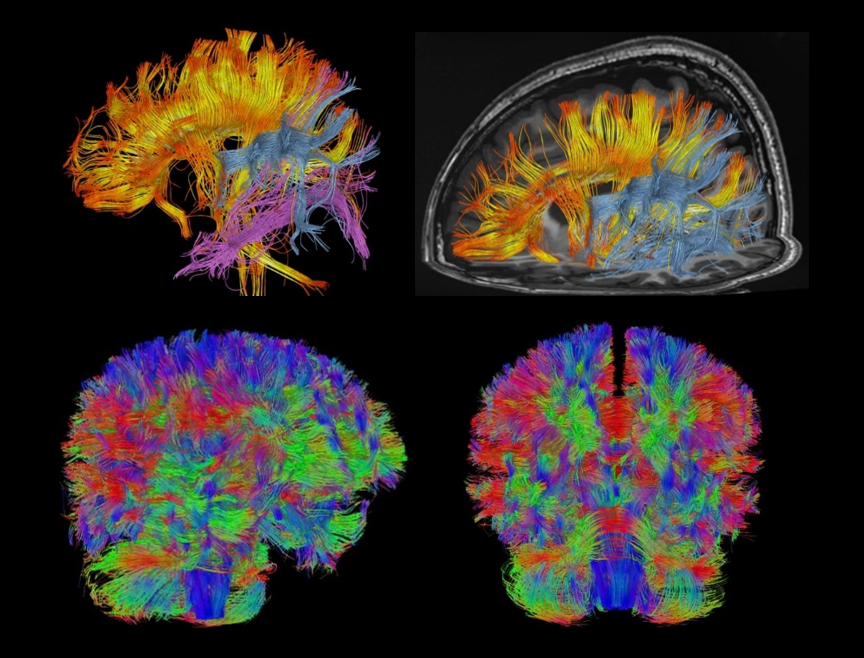

uAIFI QScan

ACS와 DeepRecon의 향상으로 인해 조용한 스캔이 가능해졌습니다.

ACS (AI-assisted Compressed Sensing)는 United Imaging의 독점 MR 가속 솔루션으로 속도와 이미지 품질을 최적으로 균형있게 조화시키는 데 사용됩니다. CS, HF, PI를 결합하고 최첨단 딥러닝 신경망을 AI 모듈로 혁신적으로 도입하여 재구성 절차에 적용합니다. 이를 통해 사용자는 영상 품질을 향상시키면서도 검사 시간을 늘리지 않거나 이미지 품질을 저하하지 않고 검사 시간을 단축시킬 수 있습니다. 이는 더 완벽한 검사를 가능하게 하며, 영상의학과 전문의들의 진단가치를 높이고 환자의 편안함을 향상시킵니다.

MRI 영상에서 더 높은 가속 수준을 실현.

각 부위의 획득 시간을 100초 이내로 단축하여, 환자 처리량을 크게 향상시키고 움직임에 인한 아티팩트를 줄입니다.

작은 해부학적 구조물을 더욱 정확하게 묘사하여 진단 능력을 확장시킵니다.

MRI 검사를 견디기 어려워하는 노인, 소아 및 기타 특수 환자들에게 유용하여 검사의 성공률 증대.